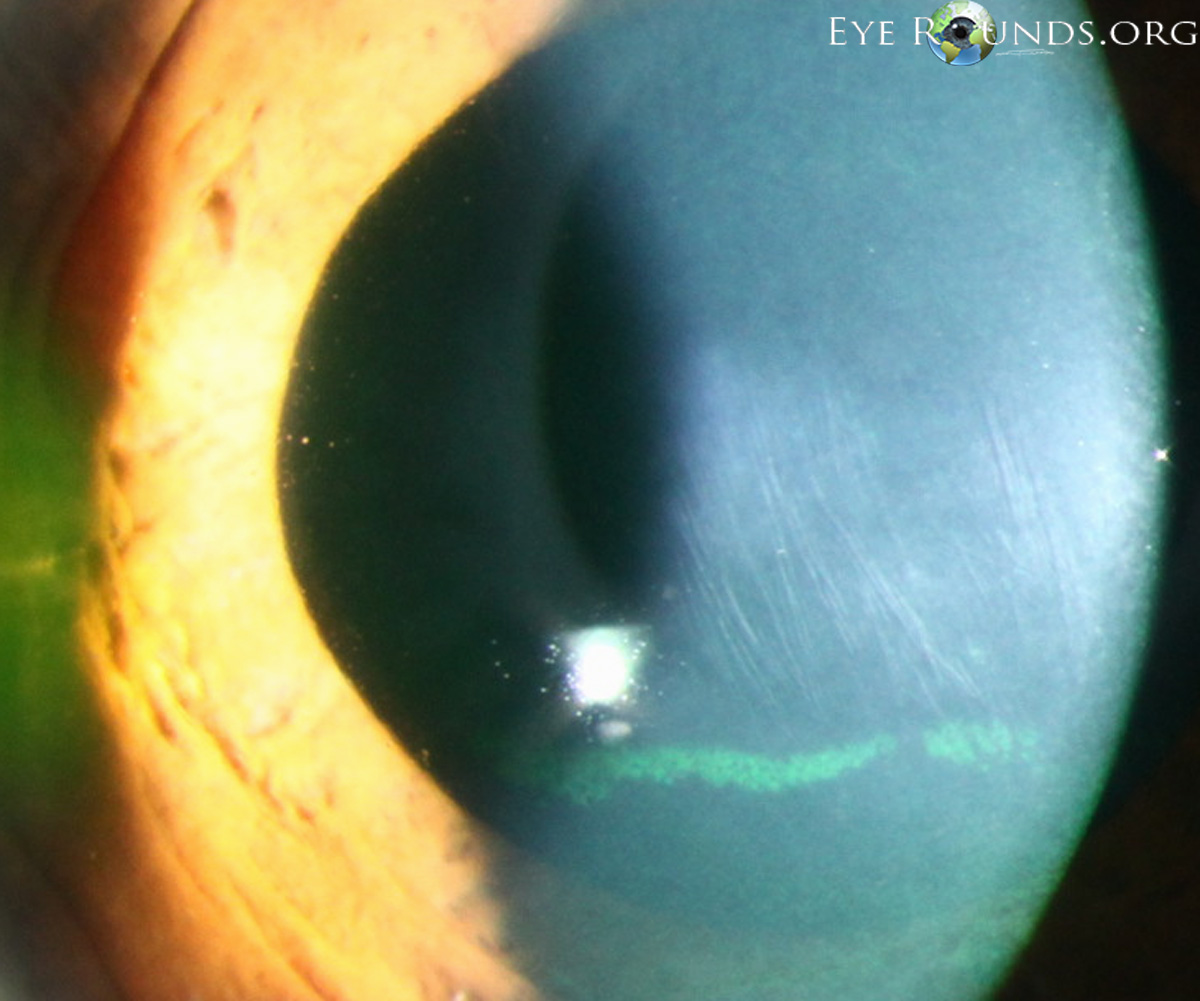

Fleischer Ring이란, 튀어나온 원추부분을 둘러싸고 철분이 각막에 침착되는 것입니다.

원추의 바닥부에 원추바닥의 가장자리를 따라서 흔히 관찰되는데,

부분적인 혹은 완전한 원형의 선이 나타납니다.

원추 주변부경계의 지표가되는데,

바닥상피에 침착된 혈철소(hemosiderin)으로 인해서 형성된것으로,

돌출이 질행될수록 점점더 고리는 더 진하게 침착되면서, 가늘어지고, 완전한 원형을 이루게됩니다.